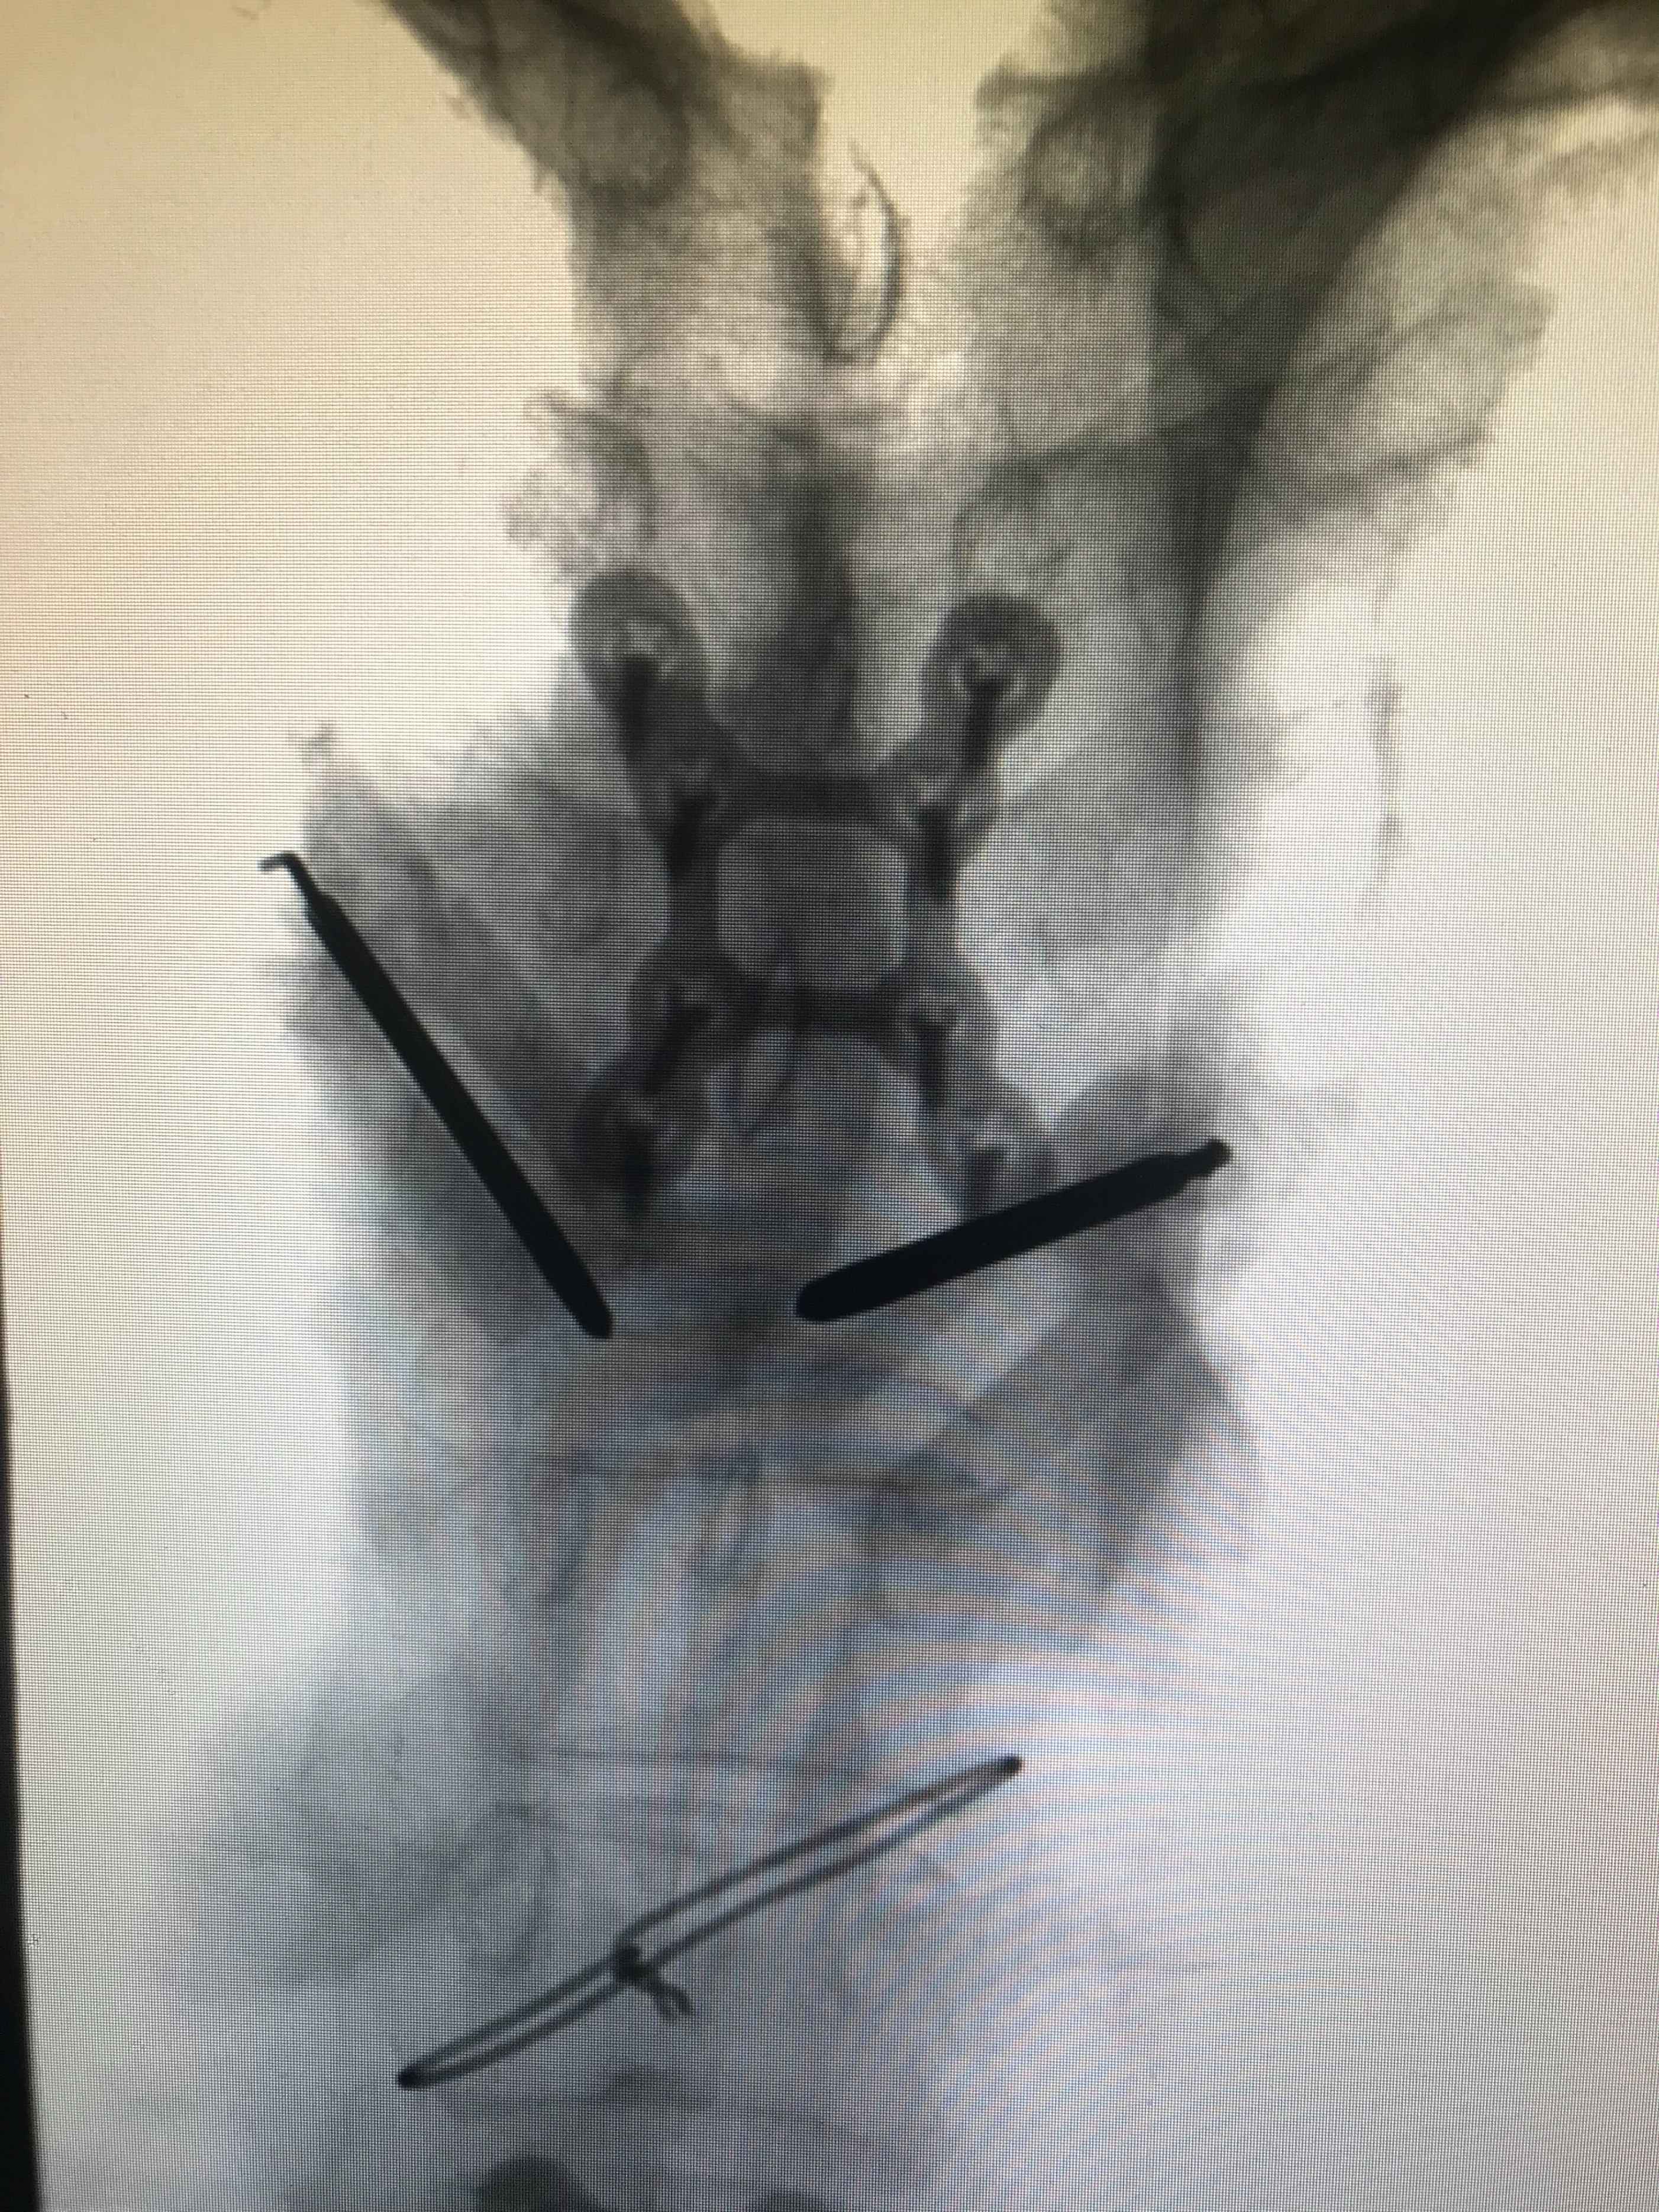

DSA引导下双侧椎弓根入路置针成功(正位)